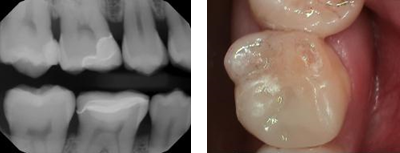

After CEREC treatment

After CEREC treatment

At Tao Dental Care, our cutting-edge digital technology allows us to

create the perfect precision restoration that will blend in

seamlessly with your natural teeth. We use beautiful tooth-colored

porcelain to precisely match the exact shade and translucency of

your teeth. Our restorative materials are strong and durable for a

smile that withstands the test of time.